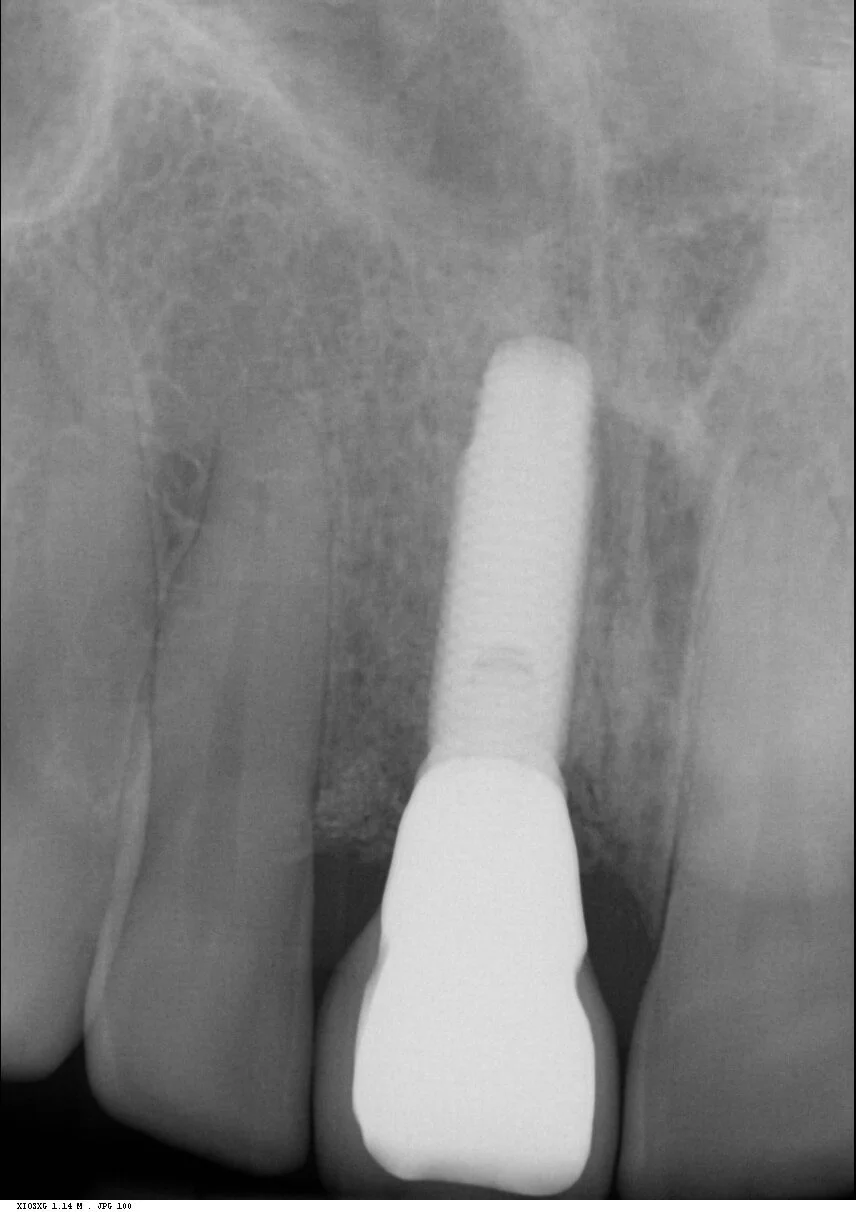

The radiograph shows extensive internal root resorption making this tooth completely unrestorable. It also shows excellent bone height into proximally both at the mesial and the distal.

Reviews carried out at both one year and then six years post operative, showed stable gingival symmetry, and the radiographs showed excellent bone level maintenance.